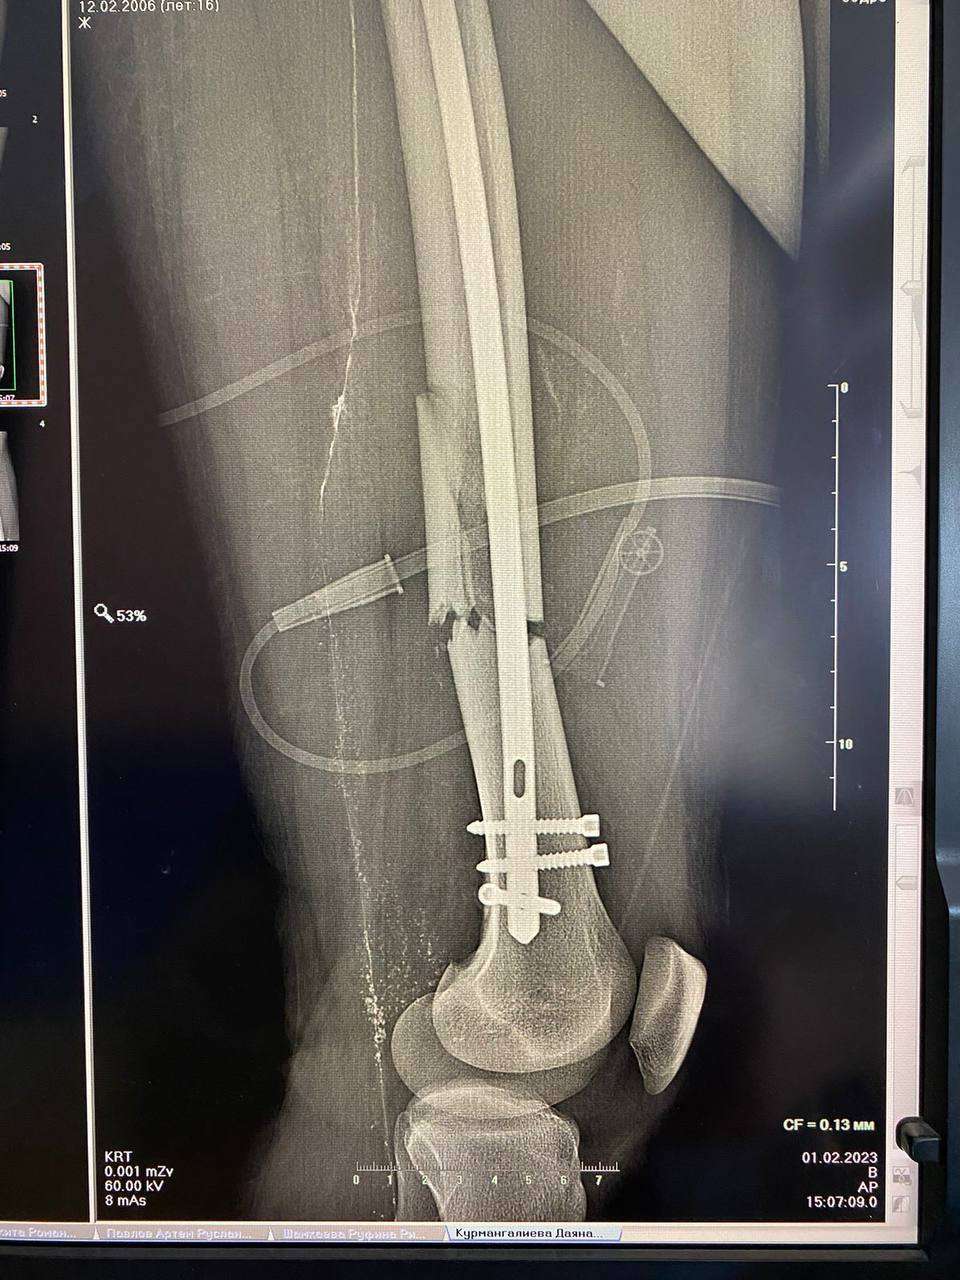

Врачи ОДКБ совместно с хирургами Городской больницы №4 сделали операцию подростку, у которого была сломана левая бедренная кость со смещением отломков.

Врачи ОДКБ совместно с хирургами Городской больницы №4 сделали операцию подростку, у которого была сломана левая бедренная кость со смещением отломков. Источник фото: ОДКБ

Пациенту провели болокириванный интрамедуллярный стержневой остеосинтез, рассказали в пресс-службе ОДКБ. Спустя два дня после операции подростка вертикализовали при помощи костылей. Болей стало меньше, а отек начал спадать.